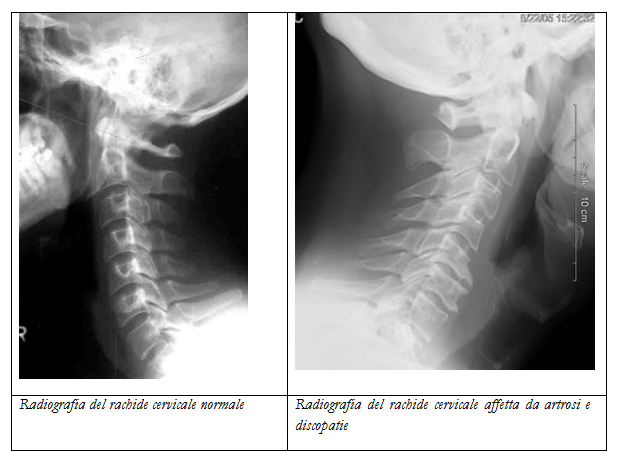

Radiografia:

Può evidenziare patologie a carico dei segmenti ossei (fratture, artrosi, neoplasie), segni indiretti di ernie cervicali (restringimento degli spazi vertebrali, rettilinizzazione del rachide), instabilità delle vertebre.